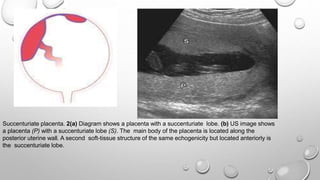

Succenturiate placenta. 2(a) Diagram shows a placenta with a succenturiate lobe. (b) US image shows

a placenta (P) with a succenturiate lobe (S). The main body of the placenta is located along the

posterior uterine wall. A second soft-tissue structure of the same echogenicity but located anteriorly is

the succenturiate lobe.